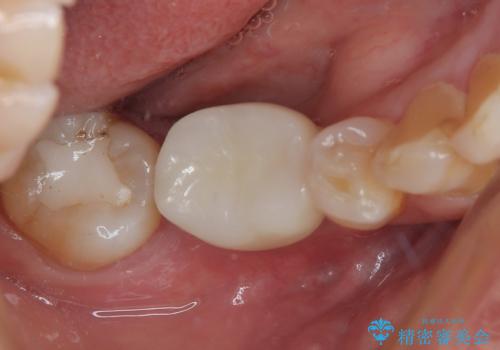

外れてしまった奥の銀歯 オールセラミッククラウンによる補綴治療